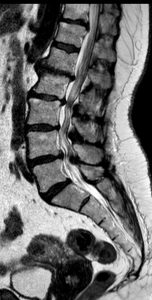

A continuación expongo imágenes de un caso prototipo donde podría estar indicado como alternativa a una descompresión y fusión larga.